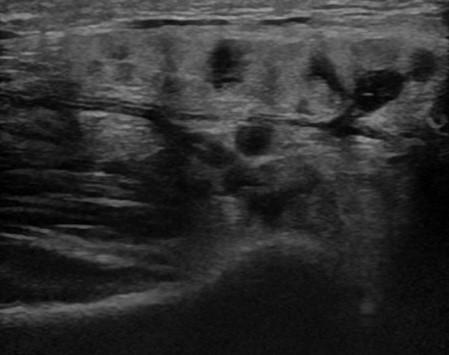

Viêm tuyến nước bọt

» Thông tin: Nam giới – 16 tuổi.

» Lâm sàng: Sưng đau vùng góc hàm từng đợt.

# Viêm tuyến nước bọt dưới hàm mạn tính.